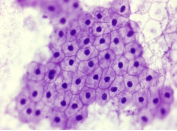

HE染色法,是苏木精—伊红染色法 (hematoxylin-eosin staining,HE) 的简写,是病理检查中最常用的染色方法。其中苏木精染液呈碱性,可以把细胞核内的染色质与胞质内的核酸染成紫蓝色;伊红是酸性染料,可以把细胞质和细胞外基质中的成分染成红色或粉红色。

细胞核和细胞质分别被染成紫蓝色和红色

一张质量好的切片可以清楚地显示不同组织的结构层次,细胞核着蓝色,细胞质着红色……。如果染色不好,红蓝不分,结构层次不清楚,将影响镜下的观察效果,直接影响病理诊断的准确性。因此,HE染色的重要性不言而喻!直接影响染色效果的因素便是染色流程,每一个步骤都很重要,缺一不可!